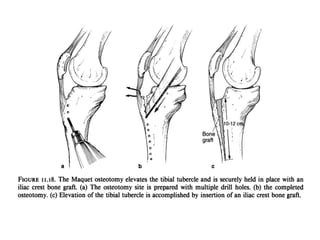

Distal Realignment Surgeries

Aims to diminish the Q angle or TT-TG distance with

anteromedialisation of tibial tuberosity and unloads

patello femoral articulation .

Indications

1. Q angle or /1" TT-TG distance > 20mm

2. Patellar alta

3. Normal patellar glide

4. Medial facet arthritis

Contraindications

1.Skeletally immature patients

2. incompetent MPFL

3. Diffuse patellar arthritis

ELMSLIE-TRILLAT OPERATION

FULKERSON OPERATION